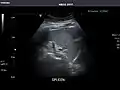

Spleen -